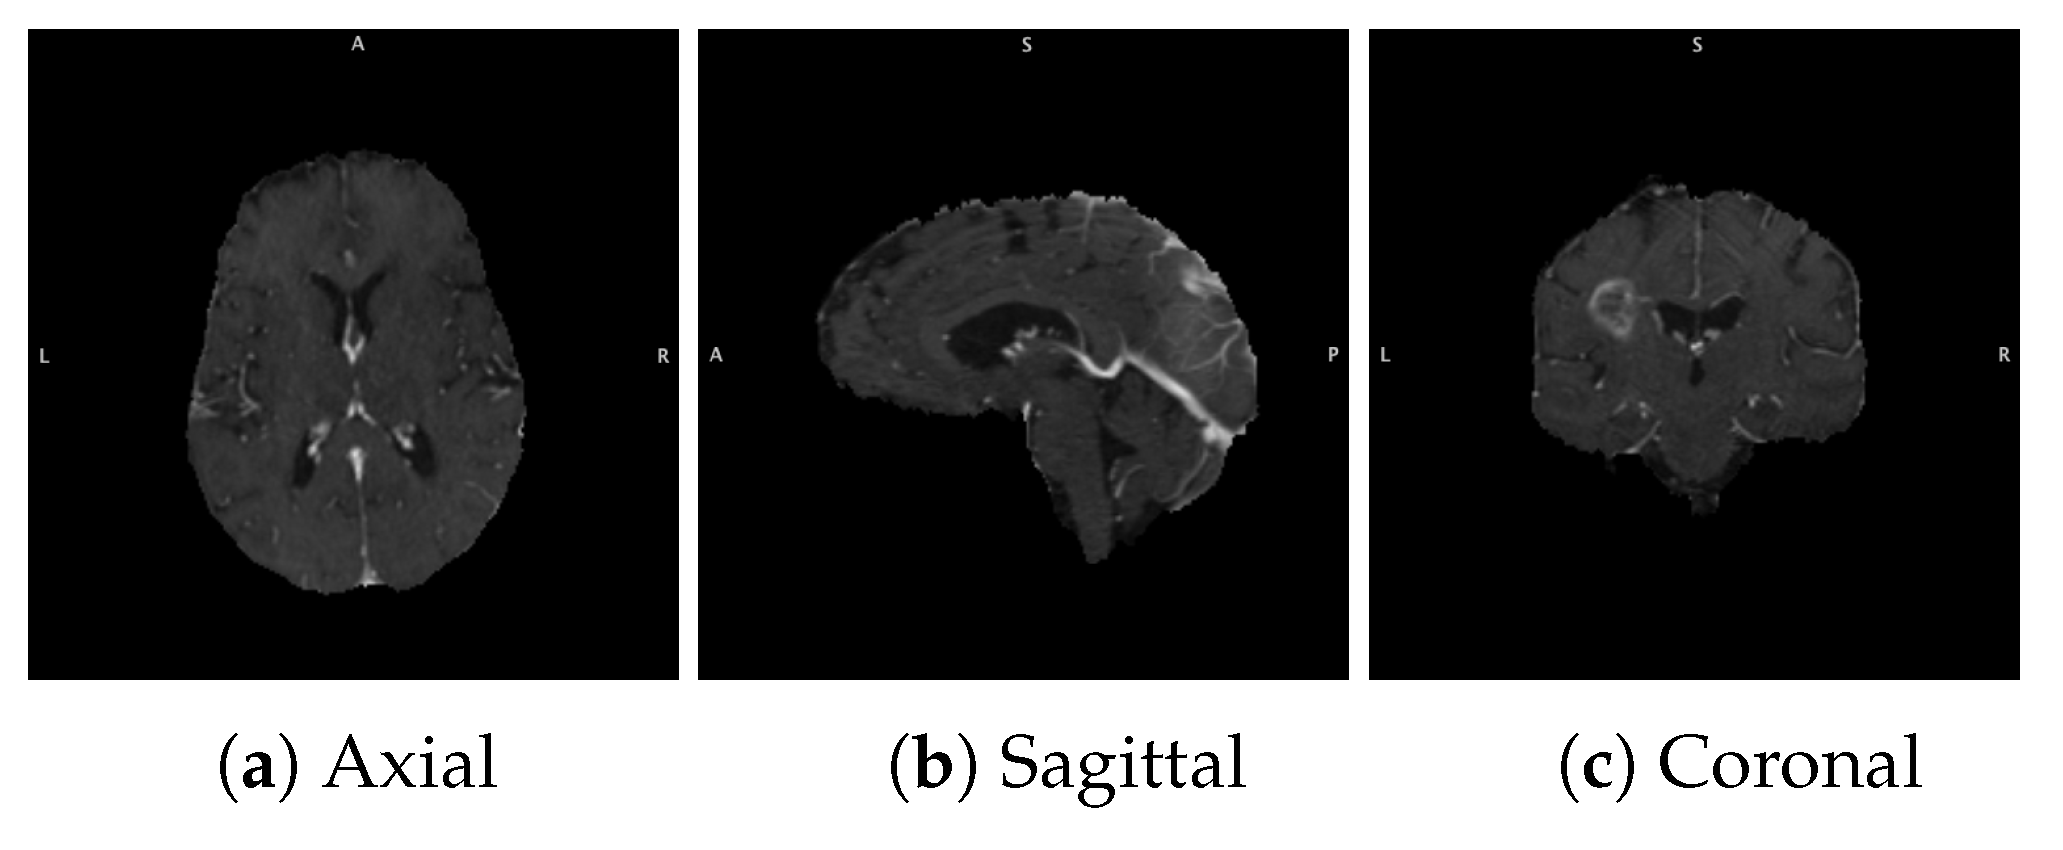

3.1. Data Acquisition and Preparation

3.1.1. BraTS Dataset

3.1.2. Data Acquisition

3.1.3. Data Pre-Processing and Augmentation